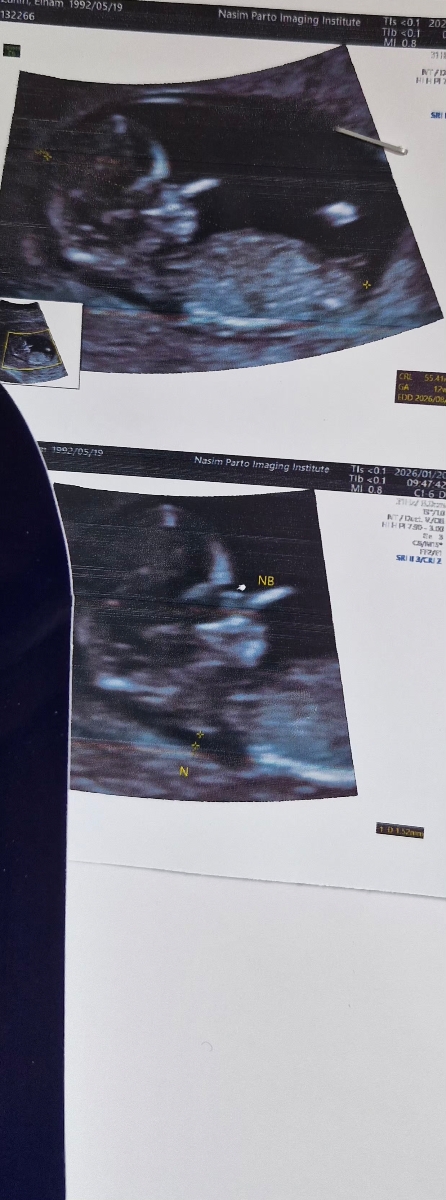

ممنون میشم سونو ان تی منو تفسیر کنید🙏

ان تی خوبه

خداروشکر همه چیز عالی است و مشکلی ندارد البته جهت تفسیر صحیح باید منتظر بخش خون غربالگری باشیم

میوم دیده شده نیز اهمیت ندارد صرفا در سونوگرافی ها باید تحت نظر باشد